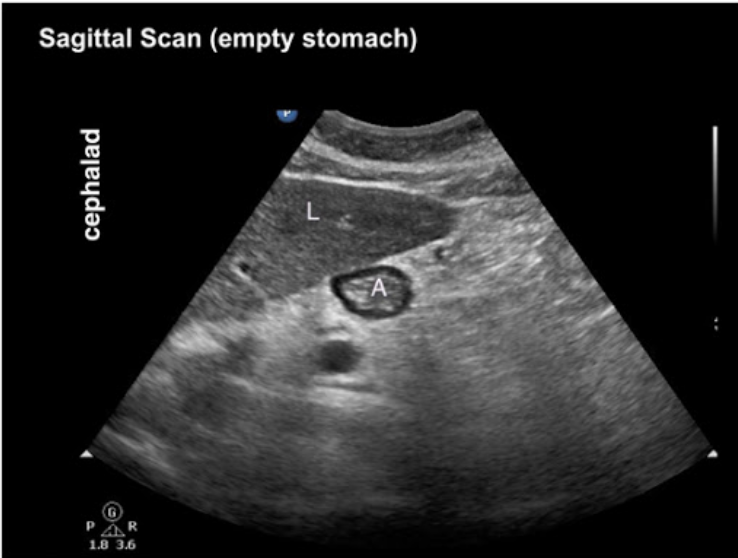

20.1 The structure labelled A shows

a. Empty stomach

b. Clear fluids

c. Solids, early stage

d. Solids, late stage